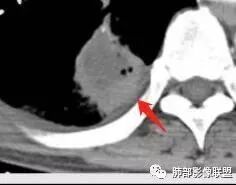

右肺下叶团块状密度增高影,边缘模糊,其内见液性低密度影,多发小气泡影及充气支气管征,考虑肺脓肿。颅内双侧顶叶长T2长T2病灶,周围水肿,DWI高信号,增强扫描囊壁环形强化,囊壁钙化,周围水肿,考虑脑脓肿。患者长期接触垃圾,什么菌都有,肺、脑脓肿,考虑肺克。再有肝脓肿就更支持了。

慢性病程,体质一般、接触垃圾,右下肺长轴与胸膜平行肿块,近肺门侧液化坏死伴多个小圆型空泡,肿块密度不均、不均匀强化,周围少量胸膜增厚,脑内多发空洞灶,考虑肺脑脓肿。鉴别肺腺癌脑转移。

胸部CT:右肺下叶背段实变,广基底,糊墙,长轴与胸膜平行,周围晕,支气管进入堵塞,纵隔窗可见低密度坏死,实变内小空洞?脑部不会看。

胸CT:右肺下叶背段实变影,内可见小空泡,病灶与胸膜呈宽基底,实变病灶周围存在毛玻璃影,纵隔窗可见病灶内存在低密度,增强可见病灶强化,并见病灶内低密度区。头MRI不会看。

右肺下叶背段实变,广基底,糊墙,长轴与平行胸膜,周围有晕,支气管进入堵塞,可见低密度坏死及小空泡。颅内多发环形强化灶,符合脑脓肿三层结构,结合临床,考虑:感染性病变,隐球菌?鉴别肺克。

肺内类三角形稍高密度病灶,边缘模糊,其内看见两个小气泡影。增强扫描欠规则厚壁中度强化,其内有轻度强化或未强化区。符合肺脓肿表现。

右肺下叶见不规则软组织影,边缘不清,内夹杂气体,背段支气管未见明显阻断,增强扫描下叶病灶内见类圆形低强化区,其边缘光滑,见低强化区壁,颅脑左侧枕叶及双侧顶叶见多发长T1长T2信号,T2高信号内见类圆形异常信号,壁呈低信号,DWI环形壁未弥散受限,内容物弥散受限,周围为水肿区,增强扫描呈多发环形强化,考虑血源型感染,颅内及右肺下叶脓肿形成

肺部病灶有收缩性,支持感染性病变,但是患者病程不急,不支持肺克

右肺下叶大片实变

我们回头看肺内的,病灶位于下叶背段,可惜没重建

近肺门区见一坏死腔,内壁较清楚,空泡在周围

单从这个坏死我们分析:1、炎性?2、鳞癌?

厚薄均匀,强化一致,未见壁结节,坏死位于病灶近端,我会首先考虑炎性

2.影像右肺下叶大片高密度影,整体边界模糊柔和,中央见圆形液化区及微小气泡影,内壁相当光整,环形强化,未见明确壁结节。双肺门及纵隔未见增大淋巴结。这样的病灶更符合细菌性肺脓肿,以肺炎克雷伯杆菌感染最为常见。